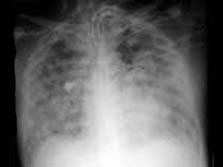

问题 该图为一羊水栓塞患者的胸片,处理原则为 ( )

选项 A、预防肾功能衰竭、预防感染 B、A+B+C+D C、抗过敏,抗休克 D、防治DIC E、解除肺动脉高压,改善低氧血症

答案 B